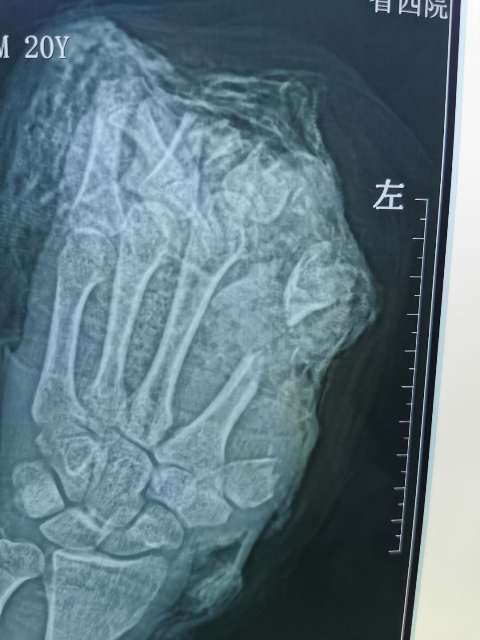

10月6日,20岁的小伙在工厂干活时左手不慎被切割机致左手拇指、示、中、环指完全离断;左小指开放伤伴肌腱神经血管离断;大鱼际皮肤软组织、环指中末节部分缺损、第一掌骨、第二掌骨部分缺损,鲜血直流。被工友慕名紧急送往六合彩生肖骨二科进行救治。

病人来院时,是晚上6时,正是大家吃晚饭的时间,骨二科(显微手外科)李会晓副主任和庞仲辉副主任顾不上这些。鉴于病人的情况危重,马上安排当班医生徐文龙和瞿超医生、立即启动应急救治预案,开通急救绿色通道,组织科室人员做术前讨论制定手术首选方案及备选方案,同时积极术前准备。“手术室、麻醉师马上准备,晚7时,一切准备妥当,手术正式开始”,患者紧急送入手术室。手术由骨二科副主任医师李会晓以及庞仲辉副主任医师主刀,在当班医生徐文龙、瞿超医生、麻醉师、手术室护士等医护员人员的通力协作下,为患者实施紧急手术。由于断指手术涉及到骨骼、肌腱、血管、神经的重建,手术难度大,特别是在显微镜下吻合细如发丝的血管(0.2mm-1mm),手术过程中不能有半毫米的偏差。

经过骨二科和手术室医务人员历时10小时,彻底清除污染失活组织及伤口内大量铁屑异物、逐步固定指骨、缝合肌腱,显微下再次清创后吻合离断神经;术中见离断动脉大部分挫伤严重无法吻合就近利用手背侧静脉,移植搭桥吻合缺损动脉完成4指离断一期急诊再植,术后经补液输血,支持,抗感染,抗凝,抗痉挛,扩血管等“三抗一扩”对症治疗。目前患者再植指体成活良好,已经基本度过危险期,保住了患者的四个手指。